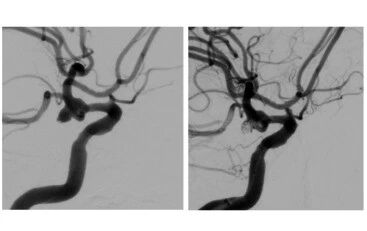

病例1——高龄危重,多学科协作显神威:(78岁女性)在家中突发意识不清、剧烈呕吐,被紧急送入我院急诊。启动卒中绿道后,迅速确诊为颅内动脉瘤破裂,且病情极为危重(Fisher分级3级,Hunt-Hess分级4级)。面对如此高龄且昏迷的患者,开颅手术风险巨大。神经外科、麻醉科、重症监护室(ICU)专家立即进行多学科会诊(MDT),一致认为急诊介入栓塞是最佳的选择。在院领导的协调支持下,各部门通力合作:麻醉科为高风险患者提供了安全、稳定的术中保障;神经外科宋立新介入团队凭借扎实技术,成功实施栓塞,封堵了破裂点;术后,患者直接转入外科重症监护室(SICU),由专门的医护团队进行严密监护和高级生命支持。在多学科的精心治疗与护理下,患者奇迹般地意识逐步转清,神经功能显著恢复,转危为安。

病例2——基础病复杂,微创介入解难题:(68岁女性)有恶性肿瘤手术史,身体条件差。此次因“突发炸裂样头痛、呕吐”来院,绿道检查同样提示动脉瘤破裂。因其无法耐受传统开颅手术的巨大创伤,神经外科宋立新团队再次展现了介入治疗与多学科协作的优势。在急诊科、影像科的快速明确诊断后,介入团队制定了周密的微创栓塞方案。导管室提供设备支持,麻醉科精准调控,确保了手术在患者脆弱身体条件下的安全进行。手术仅通过股动脉微小穿刺点完成,成功消除了再出血风险。术后,在SICU和神经外科的共同努力下,患者恢复迅速,顺利下地行走,术后仅12天便达到出院标准,彰显了微创治疗快速康复的优势。